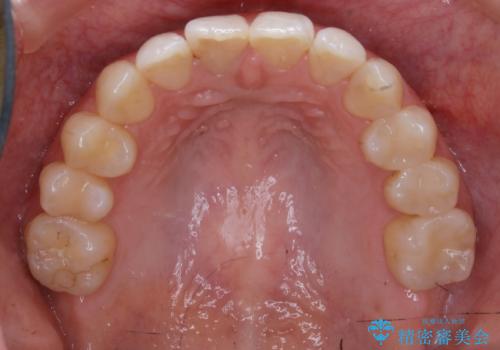

歯のガタつきをとるためのスペース作りの方法の一つにディスキング(IPR)という方法があります。

歯と歯の間を一ケ所あたり最大0.5mmまでの範囲内で削ることで歯自体が少し小さくなり、それにより作られるスペースを数ヶ所分合わせることで合計で数mmの大きなスペースが作れるという方法です。

当院ではなるべく歯の機能や見た目に影響の出ないよう、作業時に拡大鏡の使用や削るタイミングの微調整を行っています。